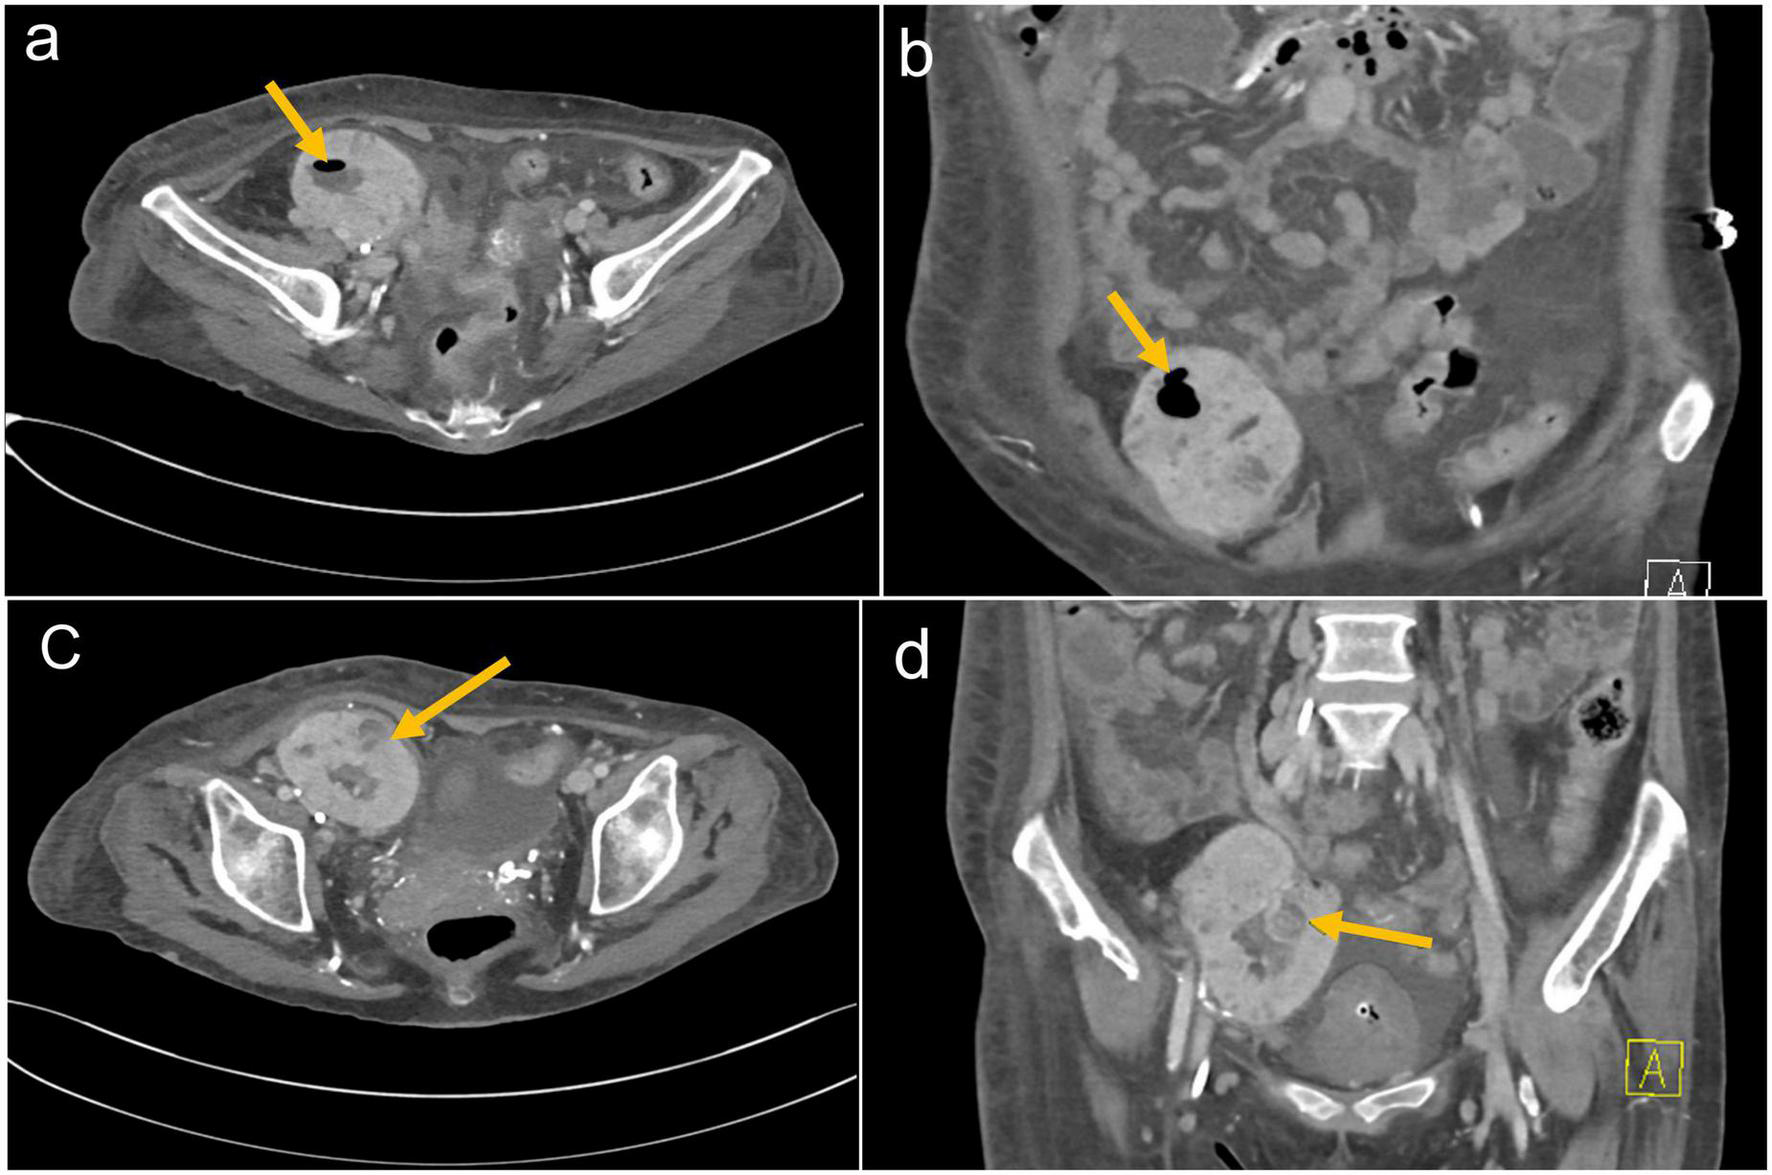

Ultrasound of the right lower quadrant allograft was suspicious of intraparenchymal gas without any hydronephrosis (Figures 1A, B). CT scan of the abdomen showed EPN involving the transplanted kidney with possible perinephric abscesses and thickening of the urinary bladder consistent with cystitis (Figures 2a–d). The patient was initiated on vancomycin, ertapenem, and caspofungin, which were later de-escalated to ampicillin-sulbactam. She received fluids and insulin for sepsis and diabetic ketoacidosis. The patient’s acute kidney injury episode required initiation of hemodialysis, which was performed with a left internal jugular tunneled dialysis catheter. Based on ongoing abdominal pain and the patient’s deteriorating clinical course, a transplant nephrectomy was performed 4 days after admission (Figures 3a, b). Kidney allograft tissue culture grew E. coli with an antibiogram similar to the urine culture. Pathology of the explant showed extensive cortical and medullary abscess formation with associated tissue destruction (Figures 4a–c). There was no evidence of acute cellular or antibody-mediated rejection. The patient’s symptoms and leukocytosis subsequently improved. Her immunosuppression was tapered off over one week. She was discharged home 16 days after admission in stable condition and on chronic hemodialysis.

FIGURE 2

(a) Axial and (b) coronal CT images of the abdomen demonstrating the right lower quadrant kidney transplant with air in the renal collecting system. (c) Axial and (d) coronal CT images of the abdomen demonstrating right lower quadrant kidney transplant with loss of cortico-medullary differentiation and developing a complex intraparenchymal fluid collection with adjacent soft tissue perinephric rind. There is debris throughout the collecting system.